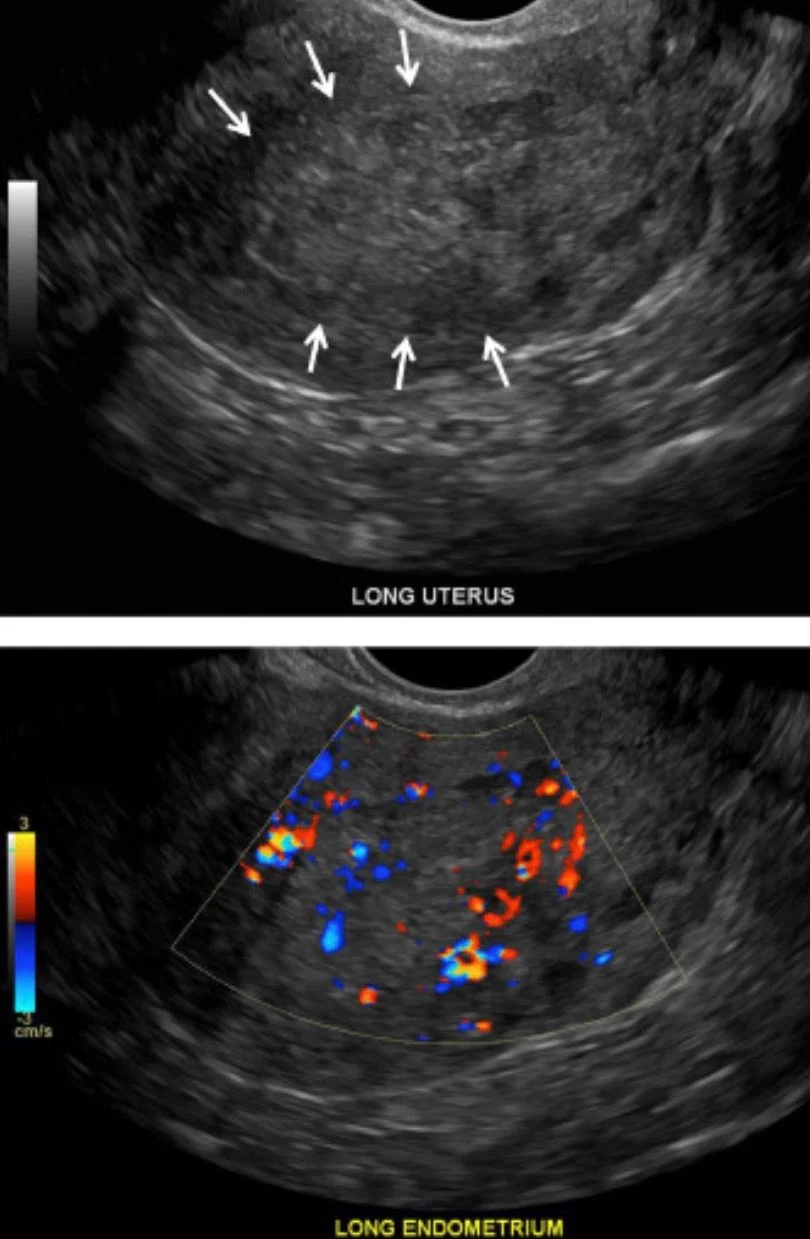

3. The Role of Doppler Imaging

Color and Power Doppler are essential for differentiating between benign polyps and malignant masses.

- Neovascularization: Malignant tumors often display ‘multiple vessel’ patterns with irregular branching.

- Resistive Index (RI): Malignant flow often exhibits low resistance.

- The Subendometrial Halo: A healthy uterus has a thin, hypoechoic (dark) zone between the endometrium and myocardium. Loss or blurring of this ‘halo’ suggests myometrial invasion.